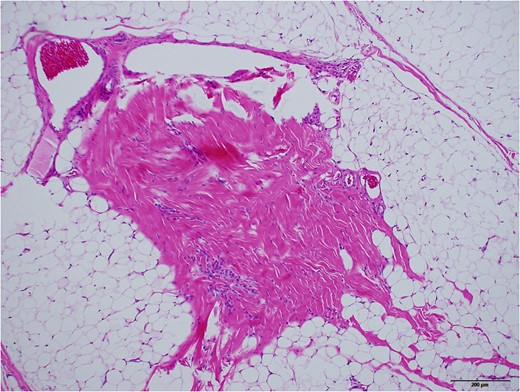

Grossly, protruded part of the mass was covered with sparsely haired skin. Sub-conjunctival part was covered with thin capsule with vasculatures (Fig. 5). Histopathologically, most part of the mass was composed of mature adipose tissue, lobuled by fibrous septum with vasculatures (Fig. 6). Outer surface was covered with squamous epidermis with normal rete ridge. In dermal layer, appendages, including hair follicles, sebaceous glands and sweat glands were seen (Fig. 7). Dense fibrous tissue was seen surrounded by the adipose tissue. This was assumed to be the link of palpebral tarsal plate (Fig. 8). No lacrimal grand tissue was identified.

Low magnification observation, taken with ×2 objective lens and stitched. Hematoxylin and Eosin stained. Black bar represents 500 μm. Most part of the tumour was composed of adipose tissue, lobuled by fibrous septum.